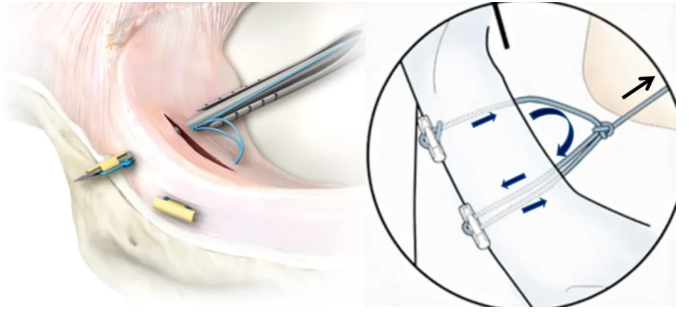

半月板撕裂主要通常采用膝关节镜下微创治疗,其目的是可以直接修复撕裂的部位,恢复半月板的正常结构和功能。

在手术中首先会修整半月板的形态使之趋于正常平整的半环状结构,最后会使用半月板缝合器对修整的半月板进行牢固和稳定以解决半月板撕裂引起的膝关节疼痛和关节软骨磨损,避免骨关节炎等严重的晚期并发症。

▲ 半月板缝合示意图